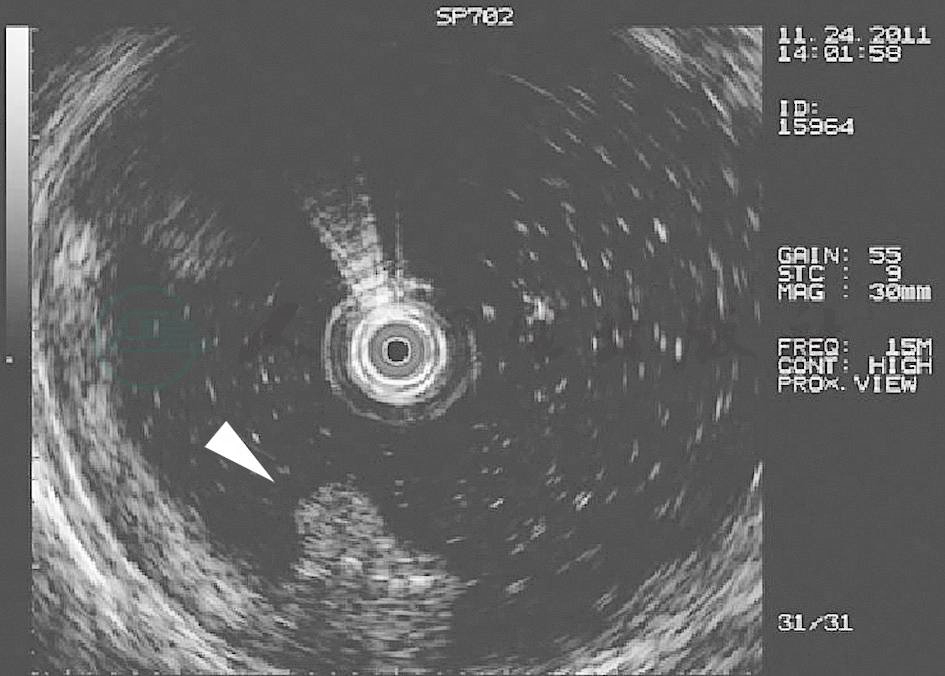

小肠镜目前尚未实现自带超声的功能,多以超声内镜探头代替(见图7),可以观察病变的深度、层次结构、有无浸润、周围脏器和淋巴结情况,可引导黏膜活检,但是对发现病变无优势,对判定小肠肿瘤的性质有一定价值。

图7 小肠海绵状静脉瘤的小肠超声表现

呈不均匀高回声